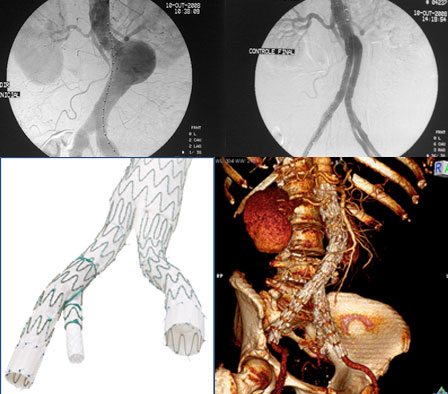

FOTO 1 – IMAGEM OPERATÓRIA DE UM ANEURISMA DE AORTA E ILÍACAS

FOTO 2 – IMAGEM OPERATÓRIA DO MESMO PACIENTE APÓS O IMPLANTE DE ENDOPRÓTESE DE AORTA E ENDOPRÓTESES RAMIFICADAS DE ILÍACAS

FOTO 3 – PRÓTESE RAMIFICADA DE ILÍACA

FOTO 4 – IMAGEM DE TOMOGRAFIA PÓS OPERATÓRIA DO PACIENTE MOSTRANDO EXCLUSÃO DOS ANEURISMAS